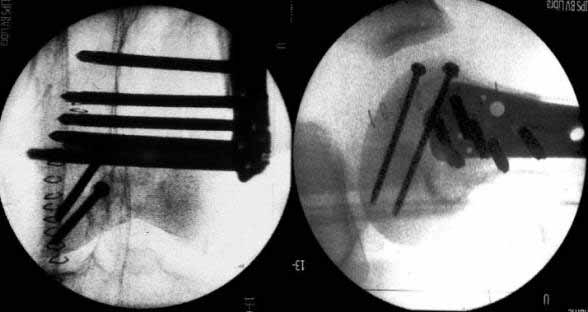

On Thursday afternoon he was alright, he is a very active man and he was moving well both knees. Later that evening he told me that while he was a little bit asleep he turned on the bed and felt pain and that the femur was loose. Here are the X-rays we took.

In this case, the fixation might have failed because of inadequate purchase of the side plate to the shaft. I say this because the initial lateral xray shows that the plate seems to be fairly anterior to the mid-axis of the femoral shaft.

Once the plate pulled off of the shaft, it continued to pull out of the distal segment. With the short unicortical screws used for shaft fixation, it is imperative that the plate be applied precisely at the midline (widest diameter) of the femur. If it is applied even slightly anterior or posterior to the midline, the screws just don t engage the cortex. You can t tell by feel, since the screws lock firmly into the plate. The only guidance that imaging provides is to visualize the plate centered exactly on the bone on a good lateral projection, which is difficult to obtain intra-operatively. I have resorted to making a 3-4 cm incision at the top of the plate so that I can verify that the plate is exactly centered over the femur at its proximal tip.

A second pearl is to place at least one or 2 lag screws between the condyles for intrafragmentary fixation before applying the LISS. Although screws were used across the coronal plane (Hoffa) fracture, I do not see any lag screws from lateral to medial. The LISS screws are designed to maintain the reduction of the distal femoral condylar mass to the shaft, but they do not function as lag screws. The intra-articular portion of the fracture demands open reduction and rigid internal fixation according to established principles; the LISS is used to then stabilize the reconstructed distal femur to the shaft.

I was taught not to put the plate in the middle of the shaft in a true lateral view of the femur, but rather slight anterior and internally rotated so the end part will adapt to the trapezoid shape of condyles, but still the screws will be in the maximum diameter of the shaft. On the post-op X-ray you can see a true lateral view of the femur (the posterior part of the condyles are aligned);but not of the plate (you can see them coming under). I can assure you that the plate was completely centered on the shaft.

On intraoperative fluoroscopy with external rotation of the thigh we confirmed that the plate was completely centered in that case.

Lateral x-ray does not adequately show proximal shaft & plate alignment with it. Do you think the plate was too anterior? This is an acknowledged mode of failure, as tangential unicortical screws may have minimal purchase, in spite of drill-tip passing through hard bone, and of course good torque as screw is tightened (into plate). If not easy to confirm intra-operatively, a short proximal incision can help to ensure correct alignment of plate with shaft.

Condyles have separated. Would separate (peripheral ? 3.5mm, lag screws, medial to lateral or lateral to medial outside LISS footprint) lag screws have been helpful? Intercondylar fracture needs open reduction and good interfragmentary compression.

LISS is a bit proximal, and screws are not parallel with joint line. Is there excessive valgus on appropriate AP views? You might want to check the mechanical axis using electrocautery cord stretched across knee, from center of femoral head to middle of talus.